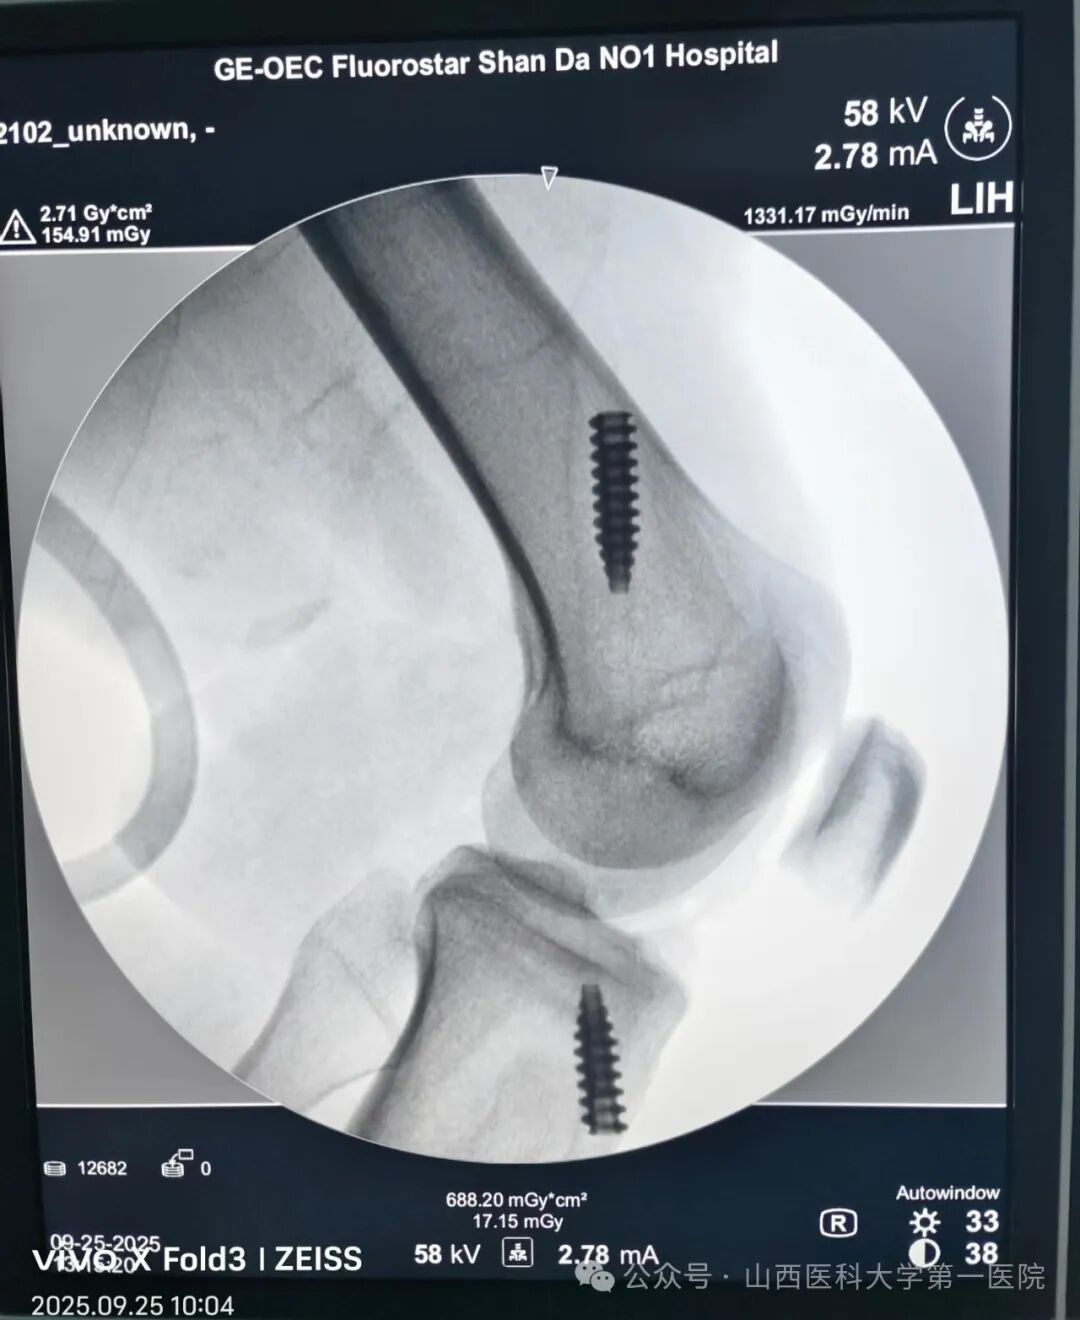

日间手术中心收治了一位膝关节前交叉韧带损伤患者,经骨科运动医学韩晓强主任医师和付永良主治医师的精准评估和诊断,决定采用日间手术模式为其进行手术和康复,这也是日间手术中心收治的第一例膝关节人工韧带前交叉重建手术。

在完善术前检查和麻醉评估后,医生开始实施手术,术中采用人工韧带对其损伤的交叉韧带进行重建(人工韧带的强度约是自体韧带的3.2倍),术后即可开始康复锻炼,有利于肌肉和关节功能的尽早康复。手术历时1小时40分钟,患者术后2小时饮水、进食并开始踝泵运动,26日早7:00下床活动,经评估于上午9点顺利出院。这是骨科运动医学专业与日间手术中心的又一次完美合作,再度扩展了日间手术范畴,提升了日间手术的病种质量。